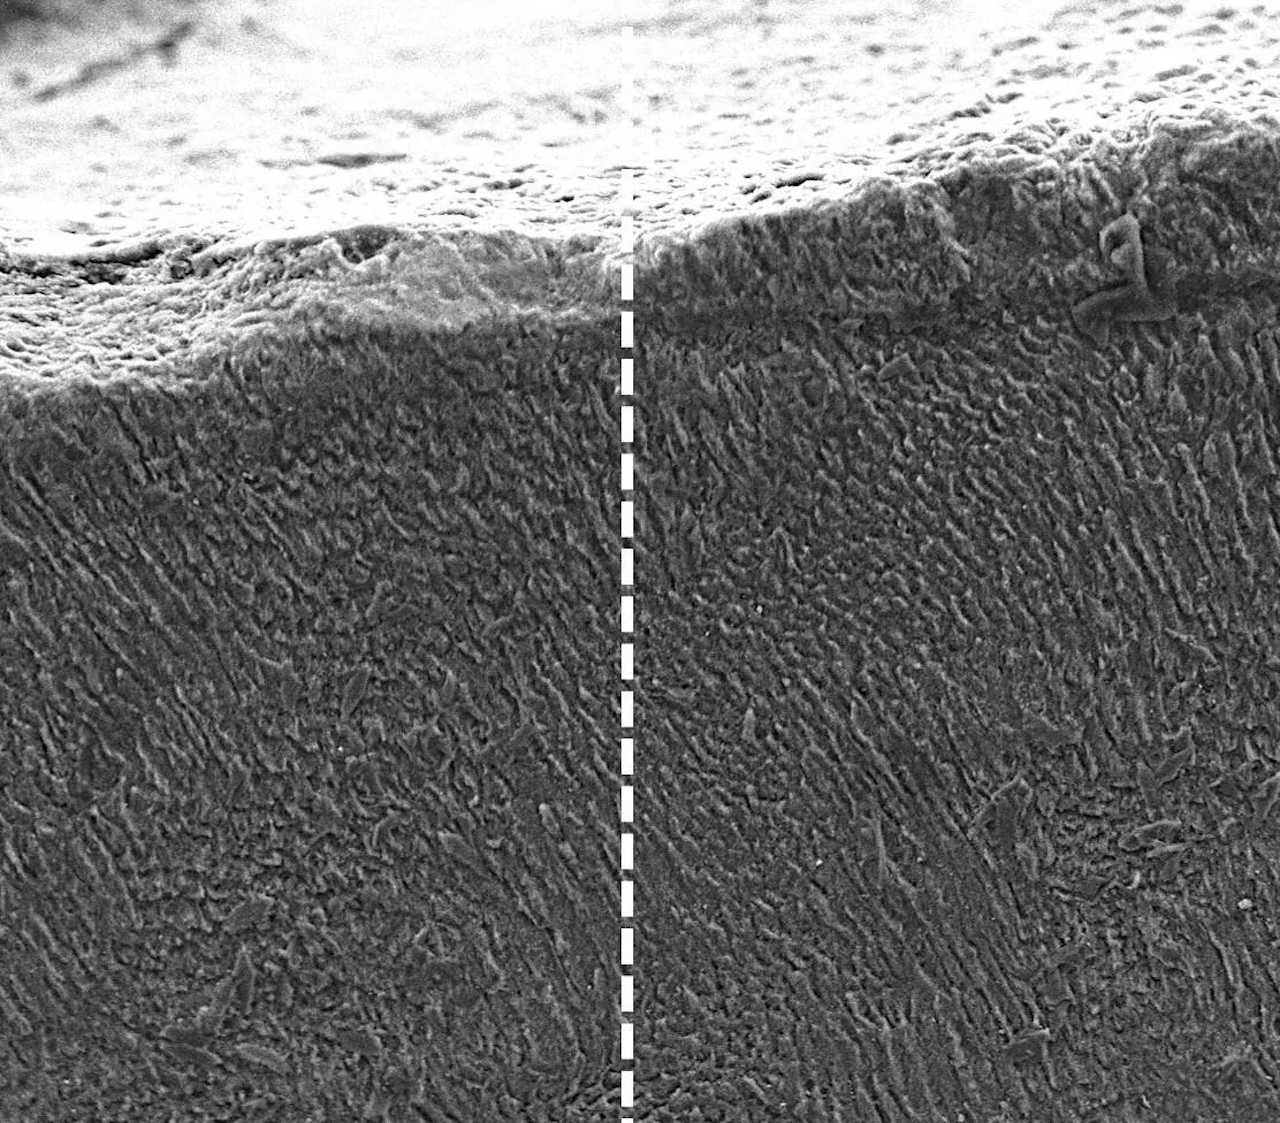

Зубна емаль до (зліва) та після (справа) обробки кератином. Після додавання кератину вона стала більш структурованою, що збільшить її міцність. King’s College London

Для дослідження науковці обрали кератин, адже у волоссі та шерсті він відіграє структурну функцію, але, на відміну від інших подібних білків, зберігає здатність реагувати з іншими сполуками. Виділивши цей білок з овечої шерсті, науковці з’ясували, що він може з’єднуватися з мінералами з довколишньої рідини. Вони додали кератин до розчину, що нагадував людську слину та містив ключові для формування зубної емалі кальцій, фтор і фосфор. Під впливом йонів цих металів білок змінив свою структуру, утворивши кристали гідроксиапатиту, що є основою зубної емалі.

Пізніше цей підхід випробували на зубах з невеликими пошкодженнями емалі, тобто карієсом. Додавання в ці пошкодження пасти з кератину сприяло відновленню структури емалі. Завдяки цьому дослідники повернули зубам не лише міцність, але й зовнішній вигляд. Хоча паста ще потребує вдосконалення та випробувань на тваринах і людях, науковці сподіваються зробити її доступною пацієнтам уже за кілька років.